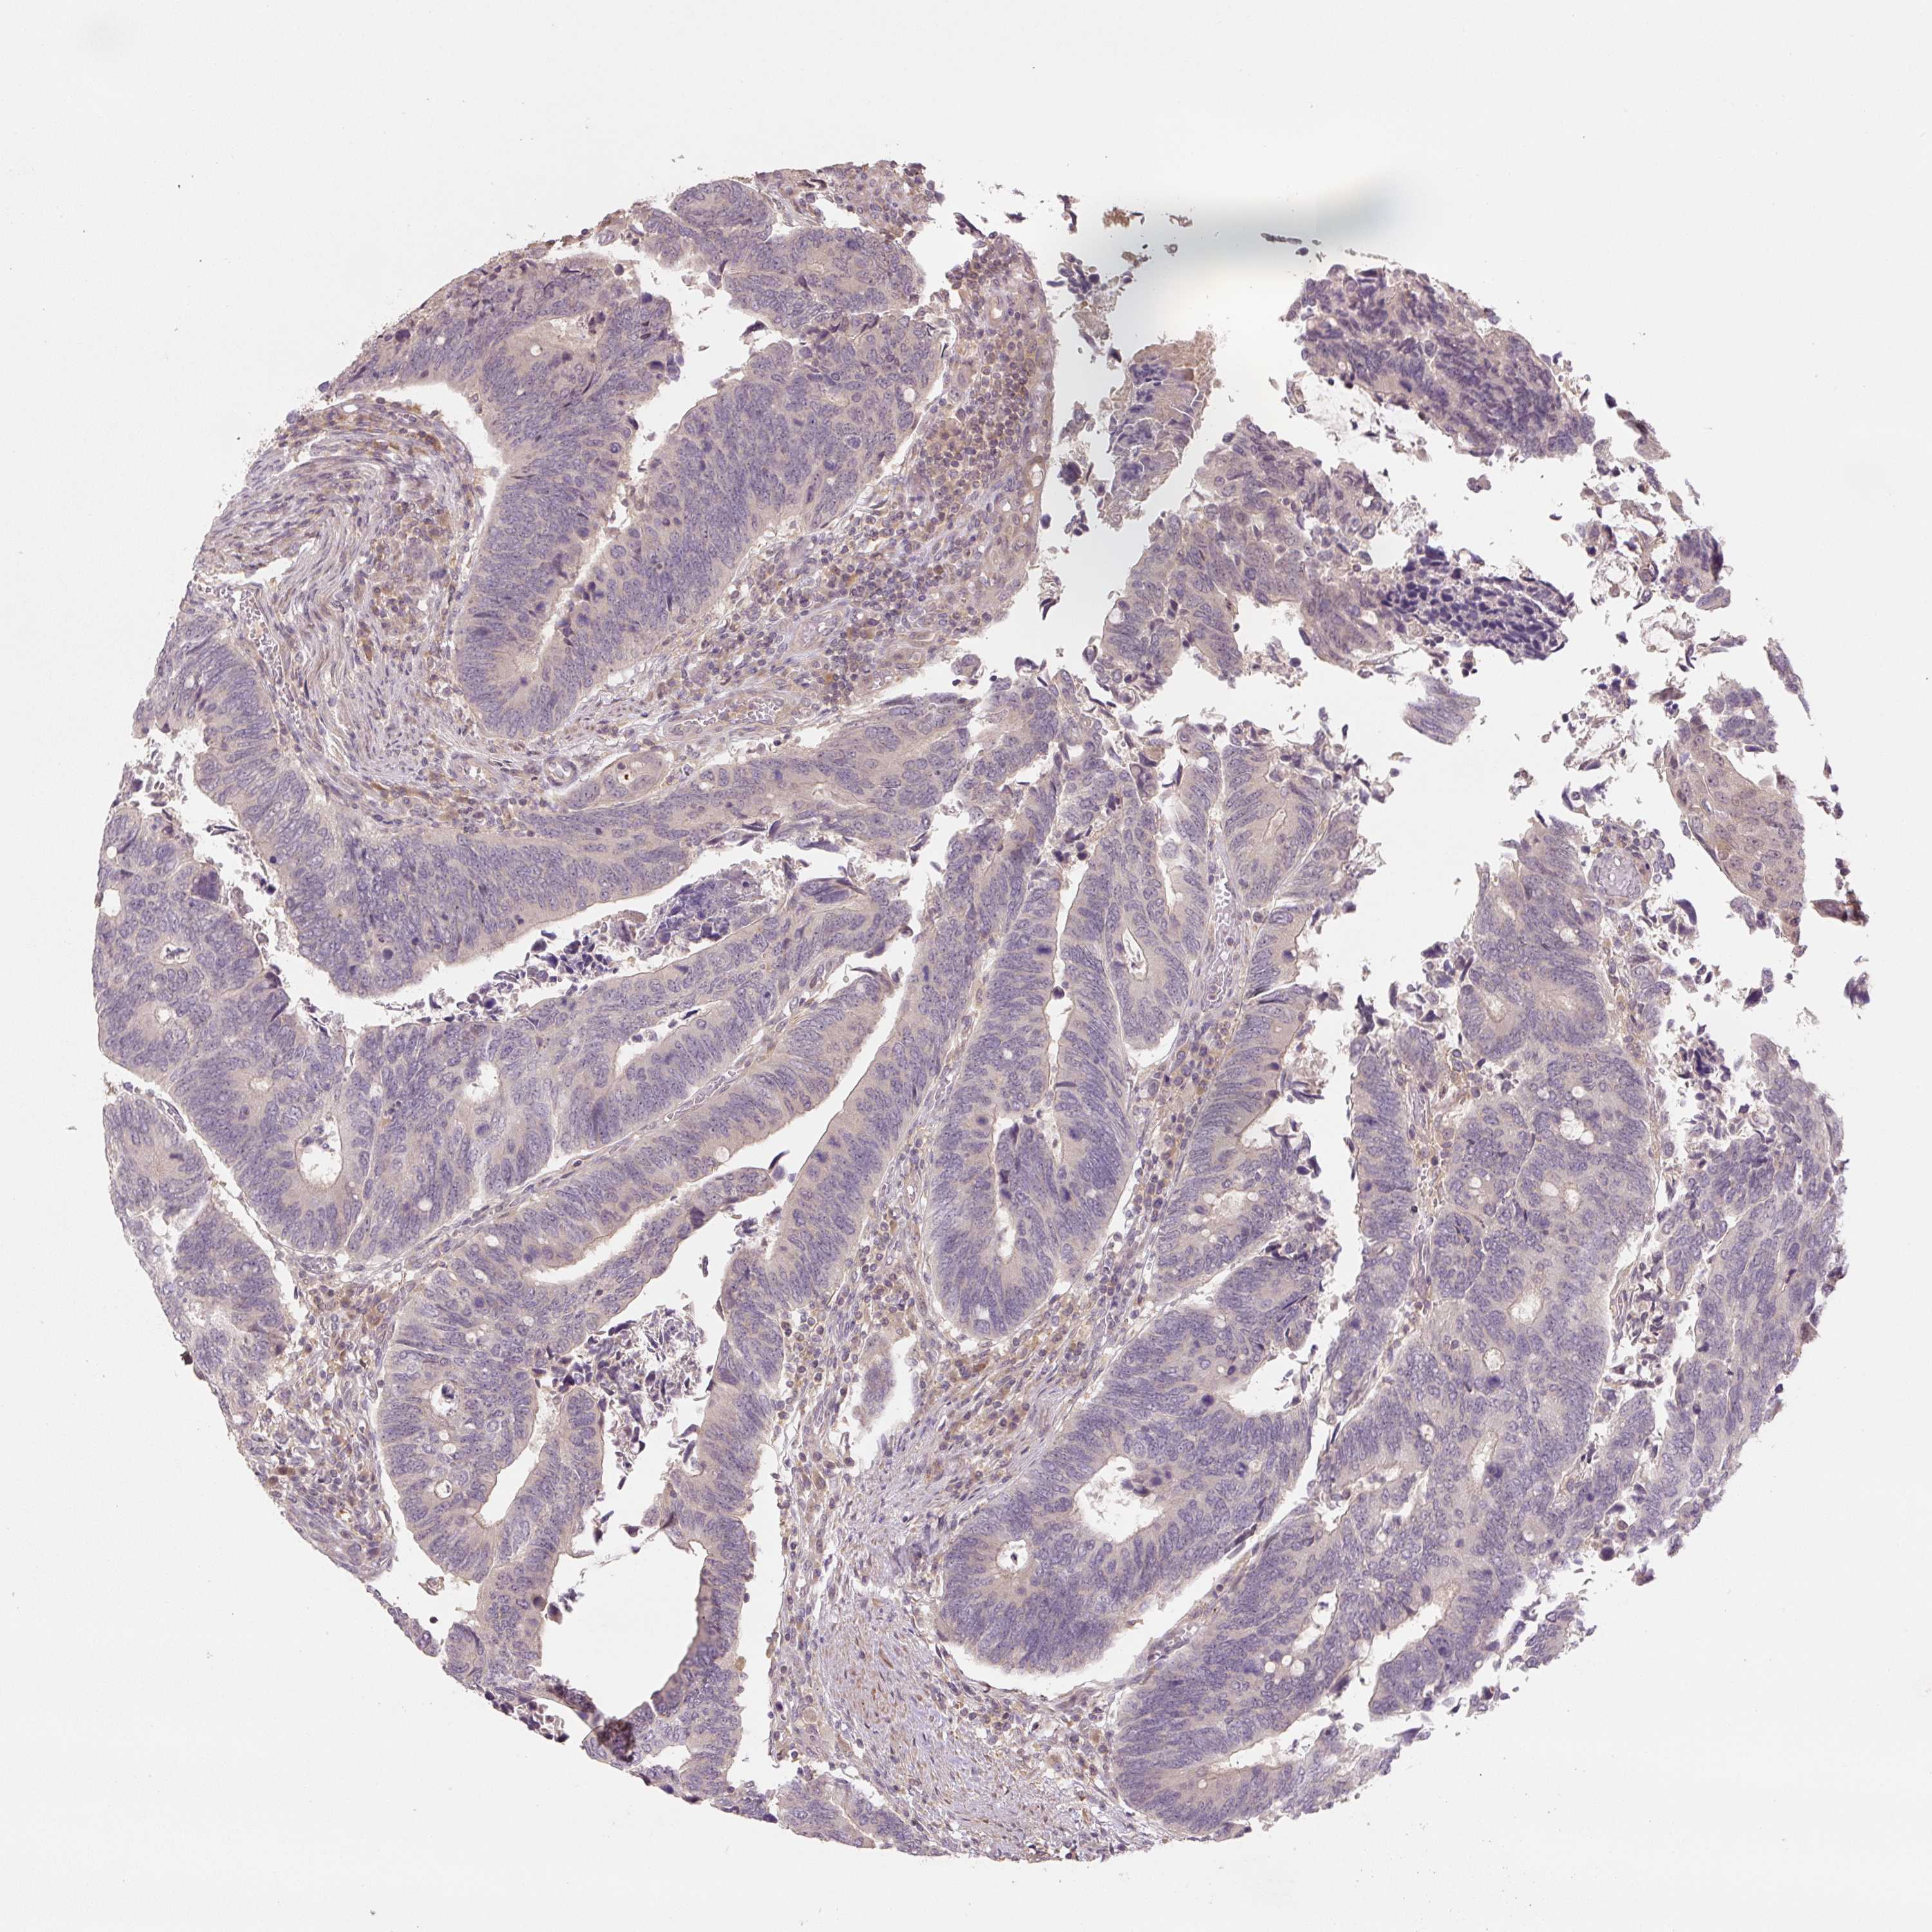

Colorectal cancer

Human cancer

Colon adenocarcinoma

Rectum adenocarcinoma